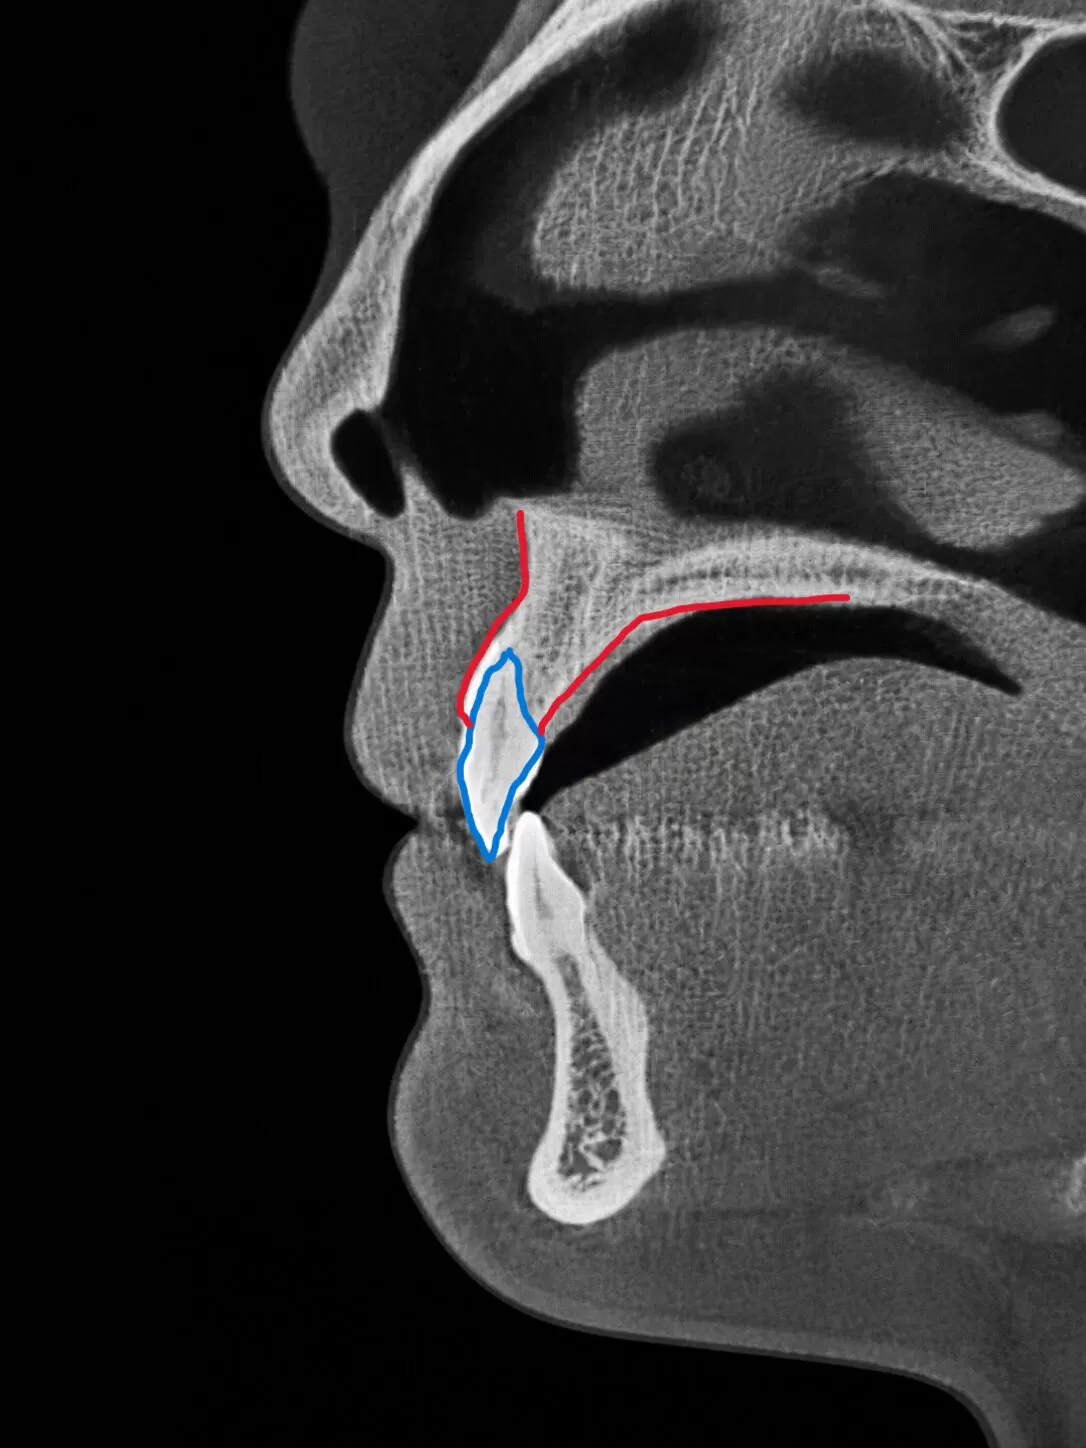

奥歯がいたいけど、どうして痛いのか歯医者さんもわからないそんな時①

こんにちは、ワイズデンタルキュアです。

先日遠方から、患者さんがいらっしゃったのですが

奥歯が痛いのに、どうして痛いのか歯医者さんもわからないとのこと

局所的な虫歯の有り無しみたいなことは説明を受けているようでしたので

全体でみてみようかな?

CTをお顔レベルで全体で!

どうですか?すごいでしょ。

これで何が起きているか見てみればいいんです。さてさて何かおかしいところがあるかなあ。